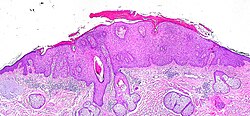

- Epidermis - outer most layer, avascular, separated from dermis by a basement membrane, epithelial tissue.

- Dermis - below the epidermis, vascular, separated from the epidermis by a basement membrane, connective tissue.

Epidermis

Layers of the epidermis

Epidermis layers - from the surface to epidermal-dermal junction:

- Stratum corneum.

- Stratum lucidum.

- Present only in "thick" skin.[4]

- Stratum granulosum.

- Stratum spinosum (aka prickle layer).

- Stratum basale (germinativum).